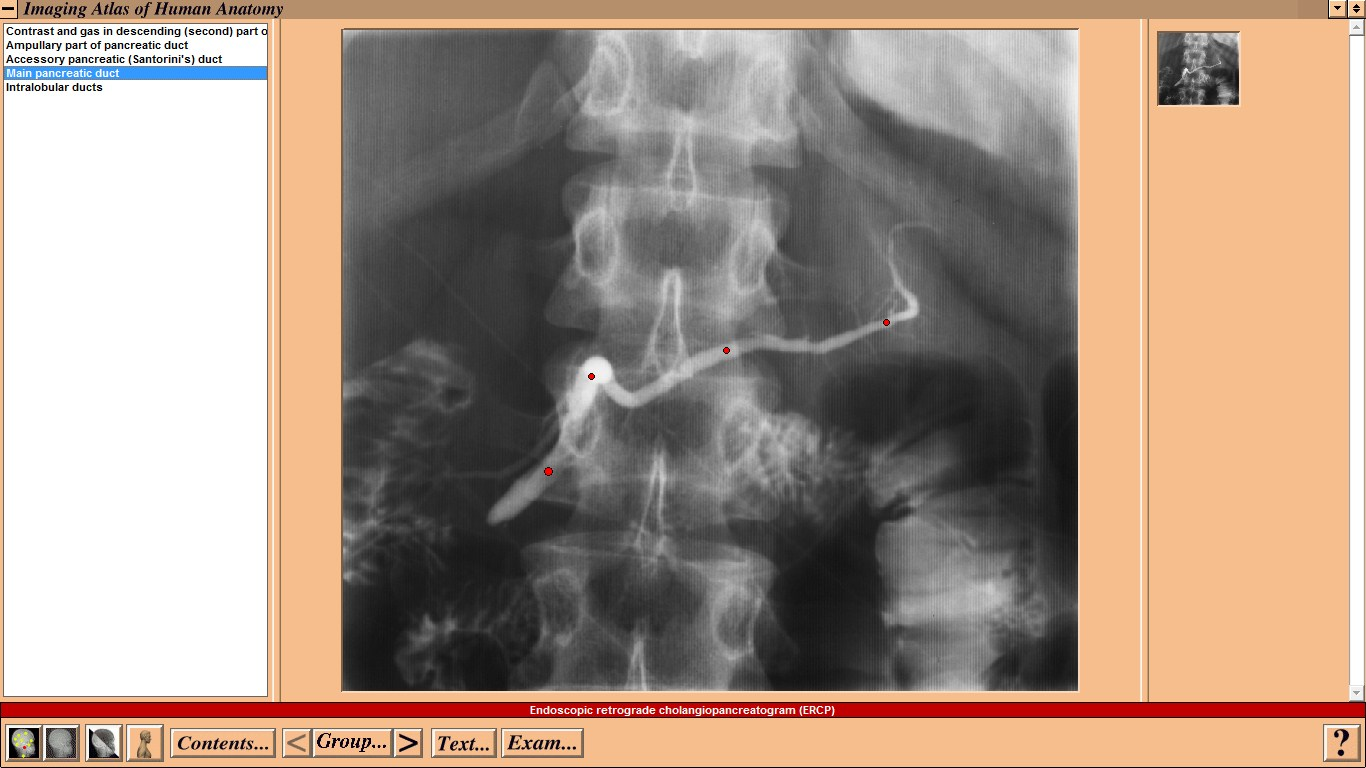

Mosby - Imaging Atlas of Human Anatomy by Jamie Weir and Peter H. Abrahams - CD-ROM Год выпуска: 1995 Версия: 1.0 Разработчик: Mosby Платформа: WindowsСовместимость с Vista: неизвестно Системные требования: IBM or compatible PC, 486SX, 8MB RAM, 640 × 480 display, 256 colors, double speed CD-ROM drive, Microsoft Windows 3.1 or later, optimum: Pentium processor, 800 × 600 display, more than 256 colors, ISBN 0-7234-2187-0, St Louis, Mo, Mosby, 1995 Язык интерфейса: только английский Таблэтка: Не требуется Описание: This CD-ROM provides a detailed atlas of radiologic anatomy in all forms, including plain films, magnetic resonance (MR) imaging, computed tomography (CT), venography, and angiography. It is formatted to present a concise atlas, cephalad (skull) to caudad (feet). The disc is easy to work with, and I did not have any trouble setting it up. The graphics and table of contents are laid out well. Navigating the various parts is relatively simple. The opening graphics are well displayed, allowing instant access to pictures or the table of contents; therein lies the simplicity of finding an anatomical part of the body to review. Each screen contains a picture of the radiograph accessed, key landmarks (with a glossary that can be turned off), related slides that can easily be accessed, and a self-exam. Диск содержит более чем 3500 радиографических изображений нормальной анатомии, включая обычные рентгенограммы, КТ, МРТ, ангиограммы, артериограммы и видео УЗИ. Исчерпывающий уровень анатомических ориентиров с возможностью самоконтроля. Издание рассчитано прежде всего на рентгенологов. Доп. информация: Поскольку издание старое, придется установить древнюю версию Quick Time - 2.0.3.51 (есть на самом диске).   Набор в группу «Хранители» - Помогите сохранить редкие раздачи неделю назад